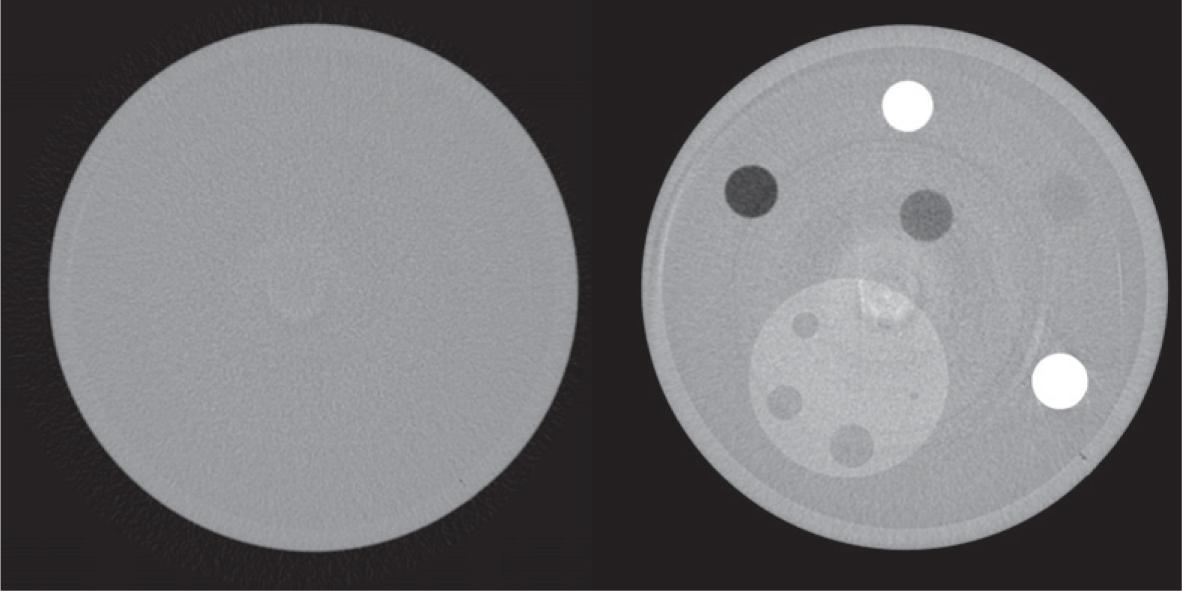

The reconstructed image has a slightly anisotropic voxel of 60×60×52 μm and is a 32-bit real, grayscale image. A subsequent 2× binning is applied to the image, with a resulting voxel of 120×120×104 µm. Finally, a smoothing filter is applied to the binned image. Exemplary reconstructed images, acquired at 38 keV and high dose, are shown in Figure 2.

Example of reconstructed water image (left panel) and detail image (right panel), acquired at 38 keV and high dose.